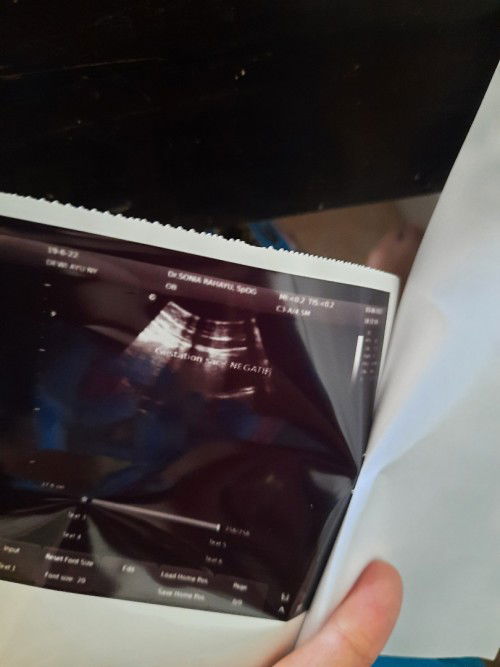

Halo bunda, ini kehamilan pertama. Waktu ugs kemarin belum tampak apapun. Rahim juga kecil kata dokter. Itupun dinyatakan negatif padahal saya tp garis 2. Dibidan katanya masik 5w. Ada saran vitamin yang saya konsumsi?

Hasil ugs HPHT 16 April, tp garis 2 tp hasil usg gitu. Ada yg sama?

Bun, aku sharing. Hbs TP 5x garis 2. bidan bilang hamil 5 minggu. Hphtnya 16 april. Tp usg gitu😭